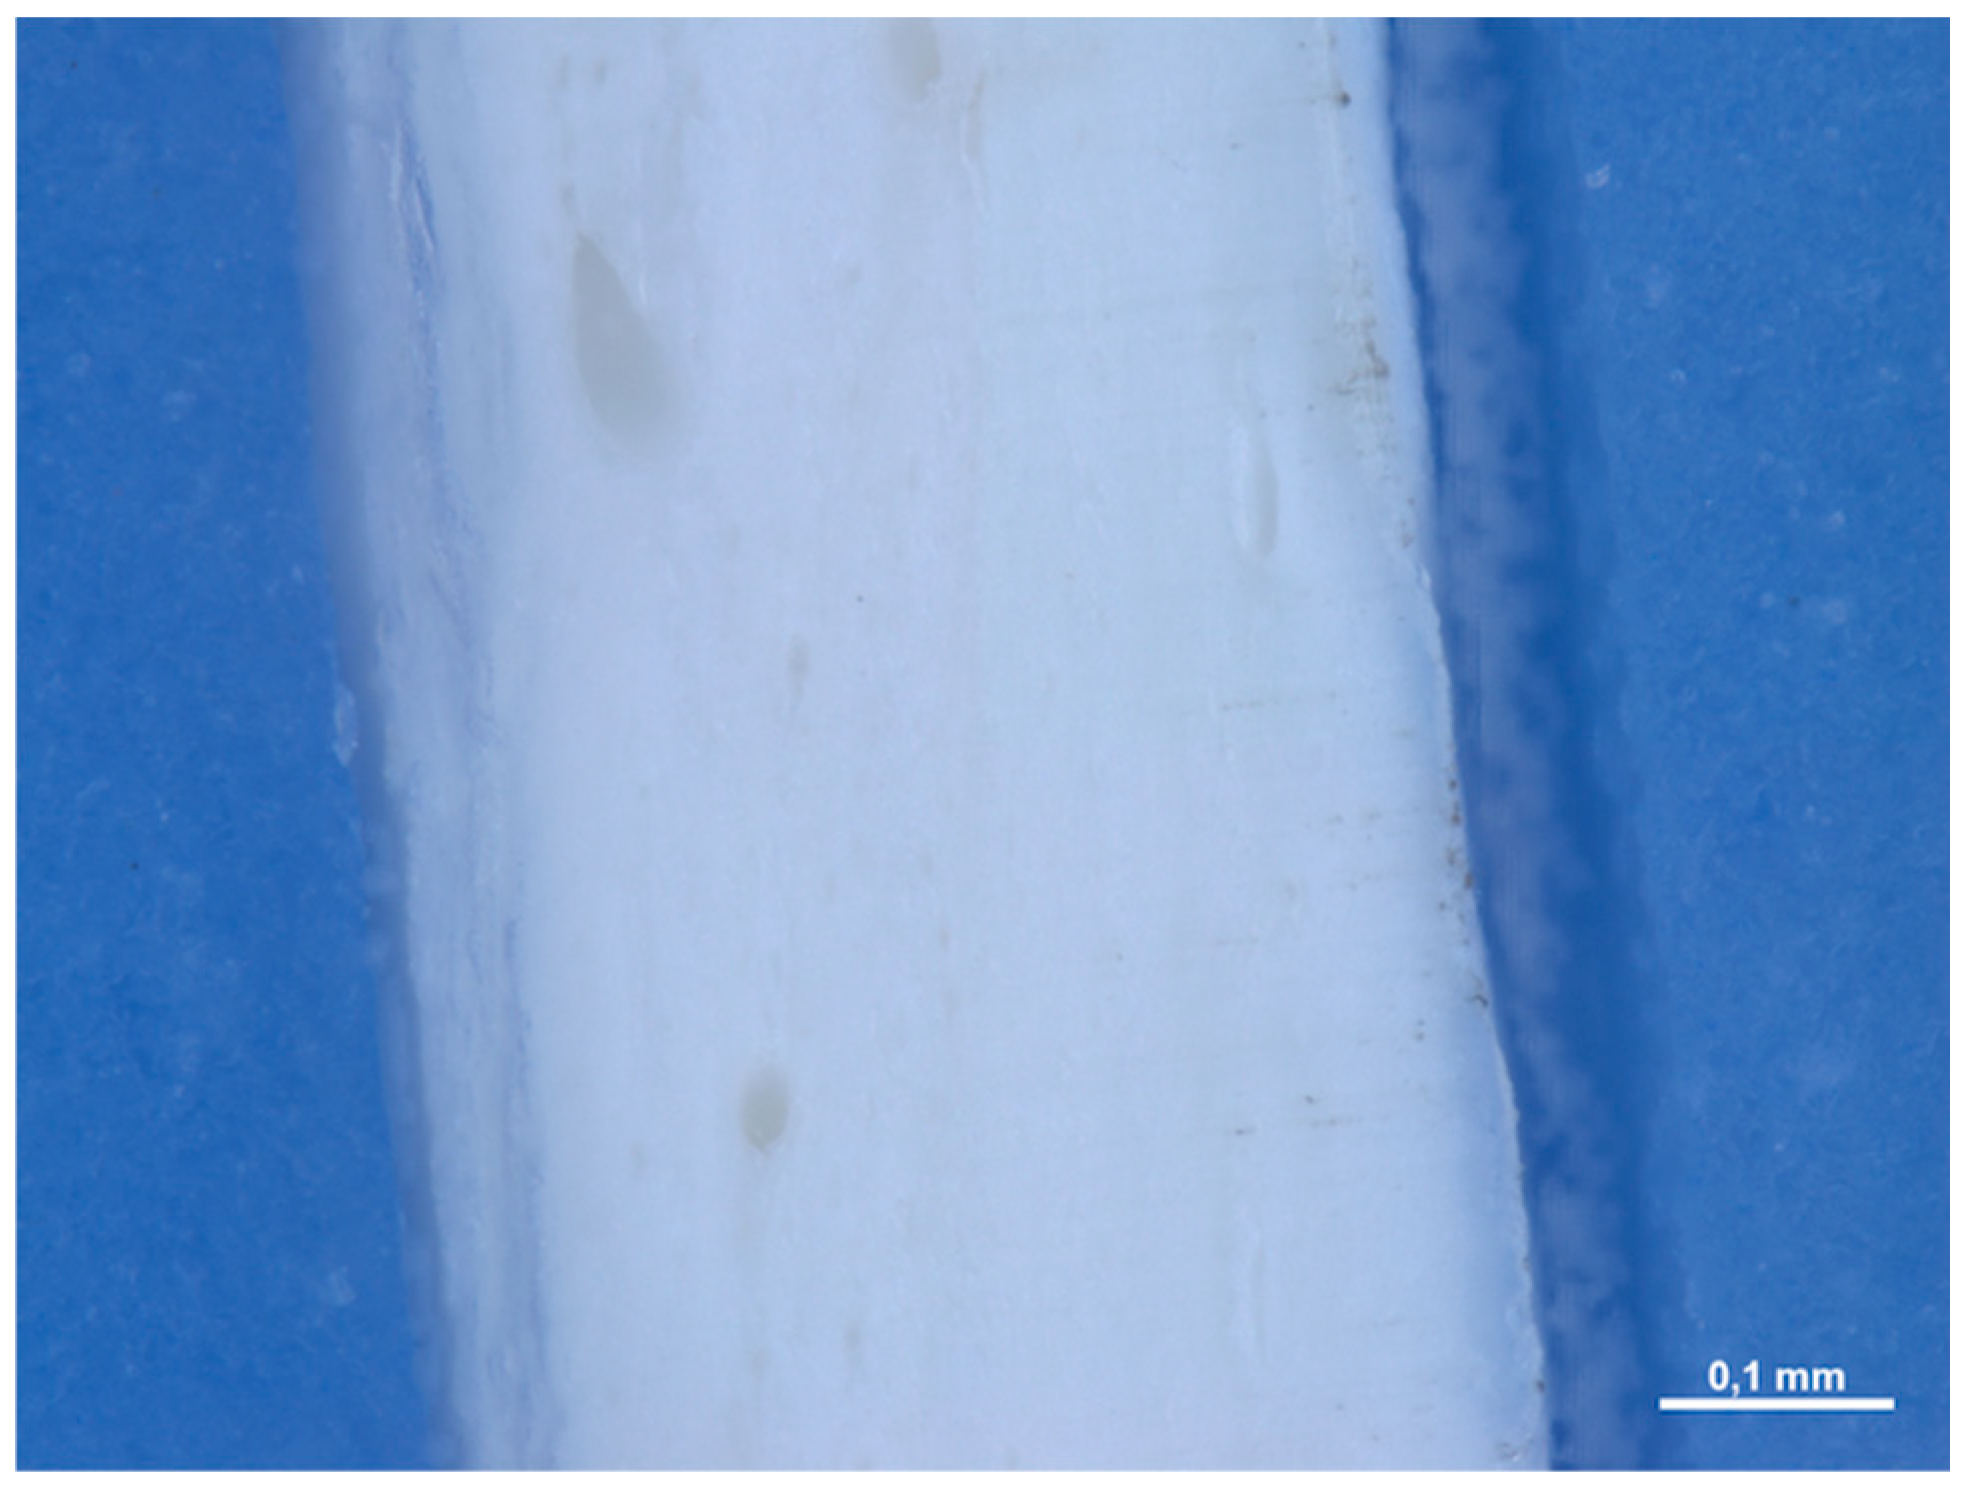

3.1.2. Optical Microscope and Scanning Electron Microscope Analysis

3.2.2. Optical Microscope and Scanning Electron Microscope Analysis

3.3.2. Optical Microscope and Scanning Electron Microscope Analysis

3.4.2. Optical Microscope and Scanning Electron Microscope Analysis

3.5.2. Optical Microscope and Scanning Electron Microscope Analysis